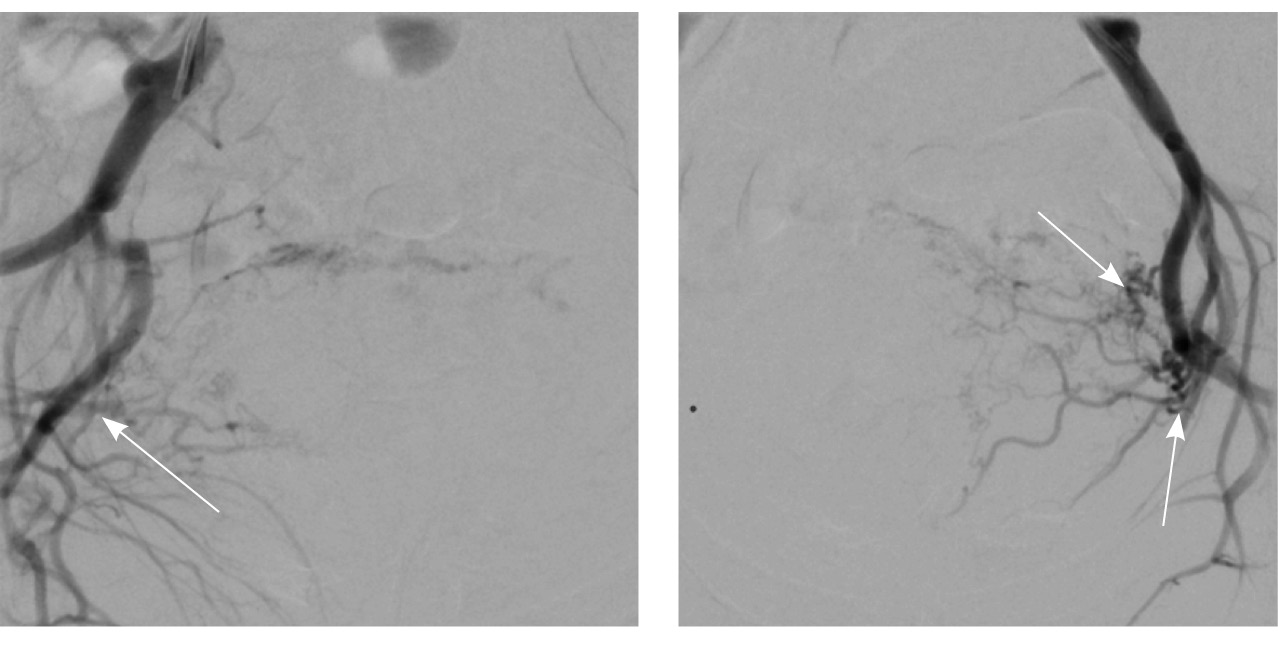

Выполнена эмболизация маточных и цервиковагинальных артерий с обеих сторон материалом PVA (1000 мкм) и эмболами из гемостатической губки. На контрольных ангиограммах патологическое сосудистое сплетение не контрастируется, артериовенозный сброс устранен (рис. 5). Катетеры и интродьюсер удалены, выполнен компрессионный гемостаз, наложена асептическая давящая повязка. Контрастный препарат йодиксанол (320 мг йода/мл) – 300 мл. Эффективная доза – 1,8 мЗв.

Рис. 5. Контрольные снимки после эмболизации маточных и цервиковагинальных артерий. Ангиограммы бассейнов правой и левой внутренних подвздошных артерий. Правая маточная и цервиковагинальная артерии, а также патологическое сосудистое сплетение в их бассейне не контрастируются, ранний артериовенозный сброс устранен. Незначительное контрастирование сегмента патологической сети по единичной мелкой ветви внутренней подвздошной артерии справа, по двум мелким ветвям внутренней подвздошной артерии слева (указано стрелками)